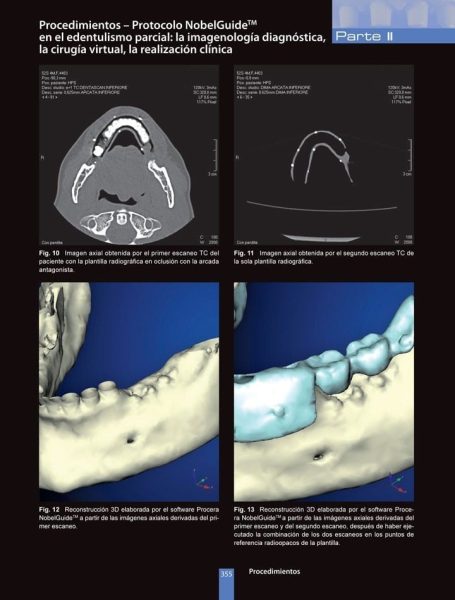

Protocolos TC Dentascan específicos del sistema NobelGuideTM